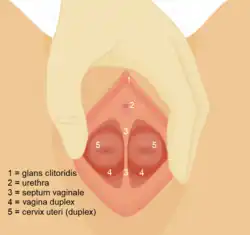

Der Uterus didelphys (von altgriechisch δίς, δί dis, di „zwei“ und δελφύς delphys „Gebärmutter“) ist eine angeborene Uterusfehlbildung mit Doppelanlage der Gebärmutter und der Vagina.[2][3]

Es handelt sich um eine vollständige Doppelanlage der Gebärmutter einschließlich doppelter Zervix und häufig auch einer Doppelung der Vagina aufgrund einer Störung in der Embryonalentwicklung, bei der die Verschmelzung der unteren Anteile der Müller-Gänge ausgeblieben ist.[4][3]

Klinische Kriterien sind:[3]

- Doppelanlage von Corpus und Cervix uteri

- meist symptomlos, gelegentlich Dyspareunie aufgrund des Vaginalseptums (in 75 %)